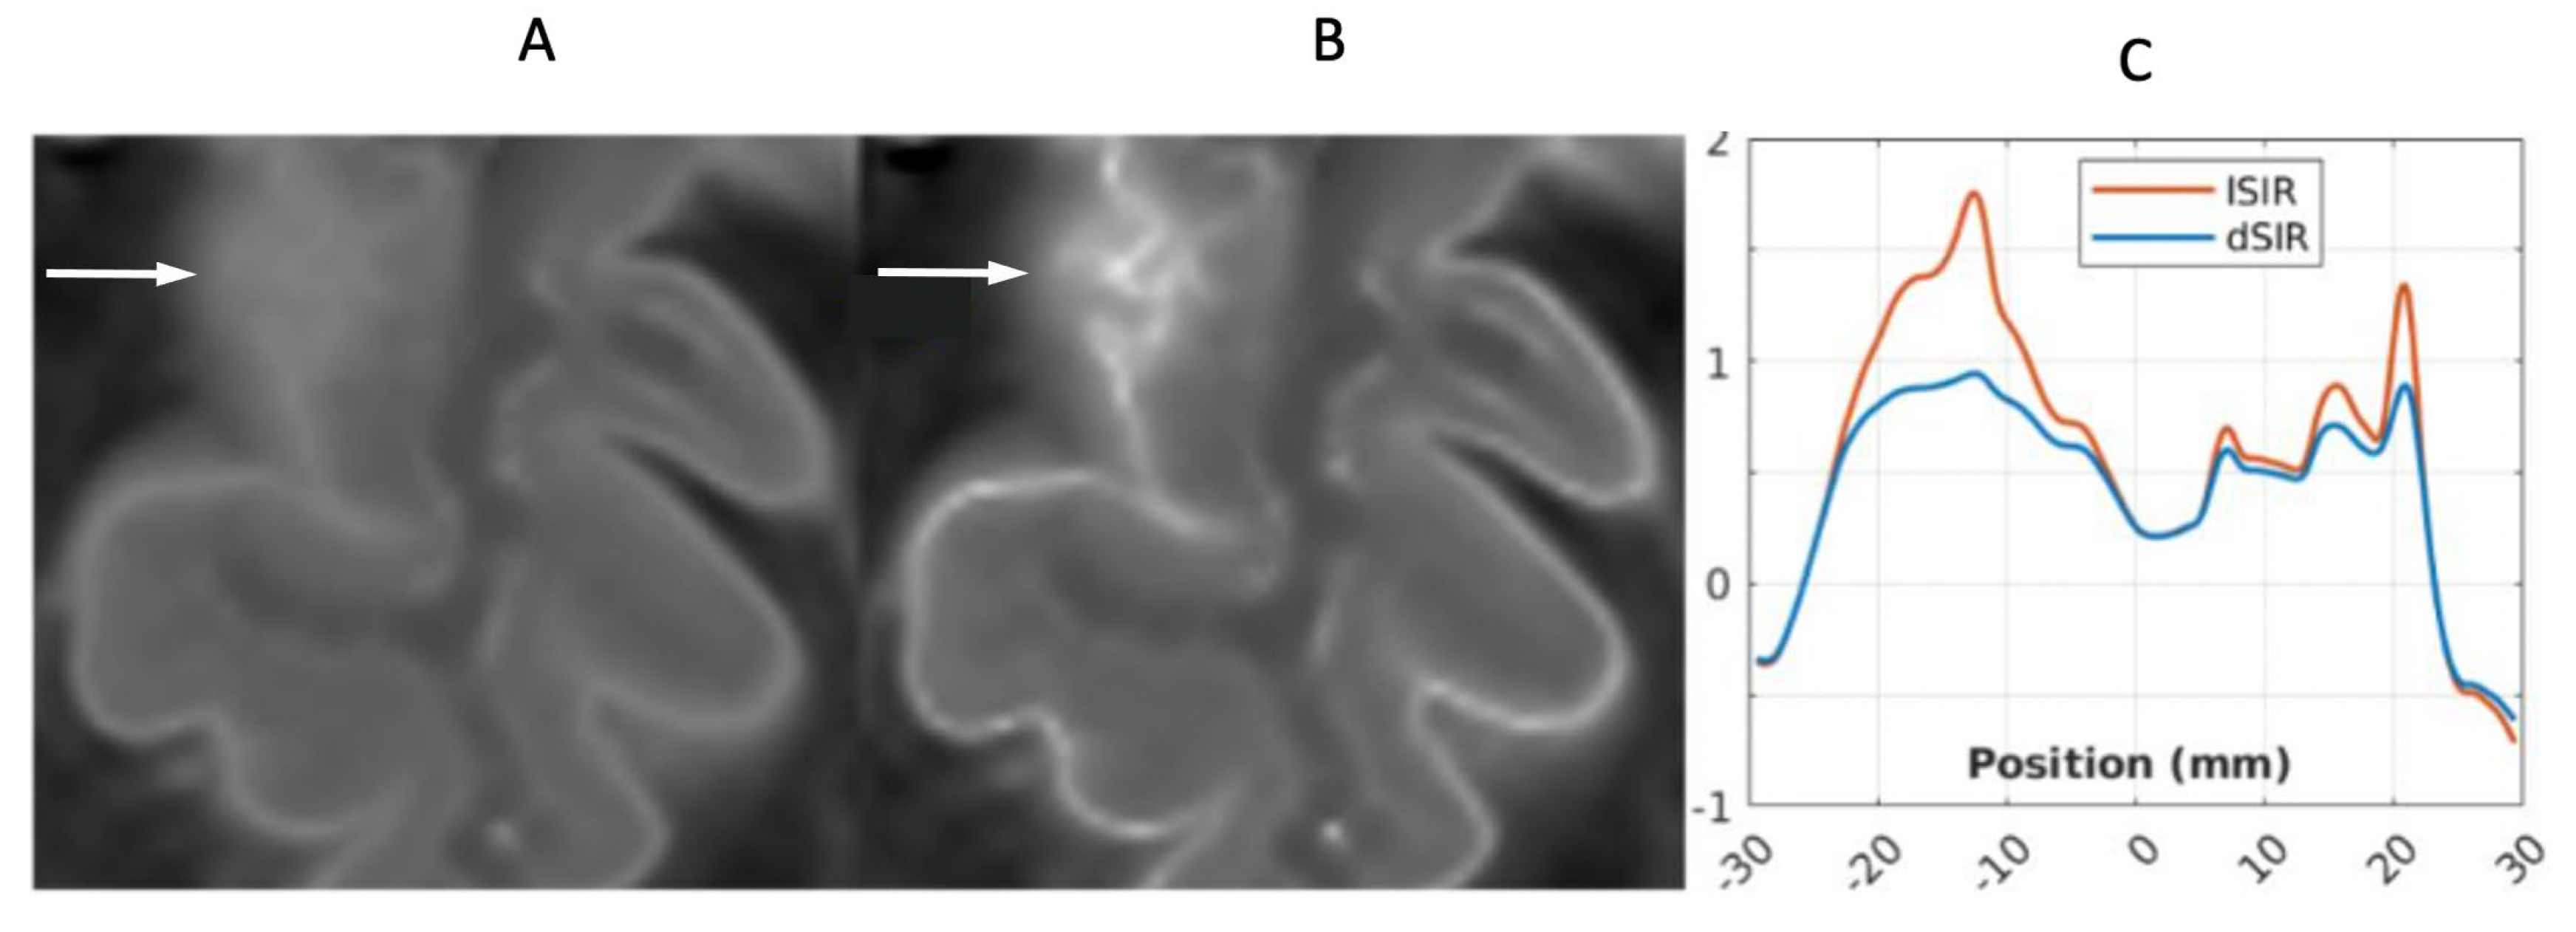

Figure 23.

41-year-old female patient with MS. A leukocortical lesion in the right medial frontal region is shown on the narrow mD dSIR image (A) and a matching lSIR image (B) (arrows). There are also left to right profiles with signal plotted against position (in mm) for the dSIR (blue) and lSIR (orange) images (C) at the level of the horizontal arrows shown in (A) and (B). No boundary between white matter and gray matter is seen within the lesion in (A). A disrupted high signal boundary between white matter and gray matter is seen in the lesion in (B). The lSIR profile (orange) has higher signal and steeper slopes than the dSIR profile (blue) in (C). The difference in signal (or contrast) achieved for the same change in position is generally greater with the lSIR filter i.e., the contrast shown on the lSIR image generally has a higher spatial resolution.